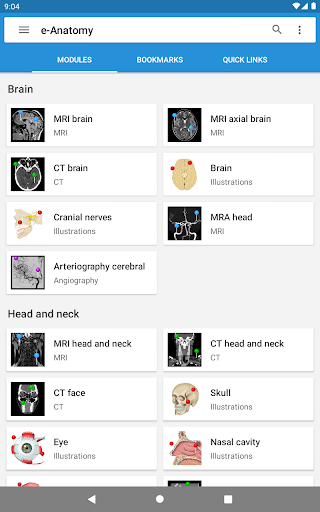

جديد: يمكنك الآن تصفية الوحدات حسب المنطقة أو نوع المحتوى حتى تتمكن من العثور على الوحدة التي تبحث عنها بشكل أسرع.

- وحدتان جديدتان: الدماغ - TOF والأوعية الدموية الدماغية ، أطلس التشريح الوعائي العصبي الطبيعي لشرايين الدماغ على الأوعية الدموية الدماغية. - تم إعادة صياغة الواجهة. - تتوفر علامة تبويب جديدة باسم "QuickLinks" ، ترسل وحدات في أقسام من جسم الإنسان وتسمح لك بالسفر السريع إلى الوحدات التي تبحث عنها. الخلل الصغيرة الثابتة.